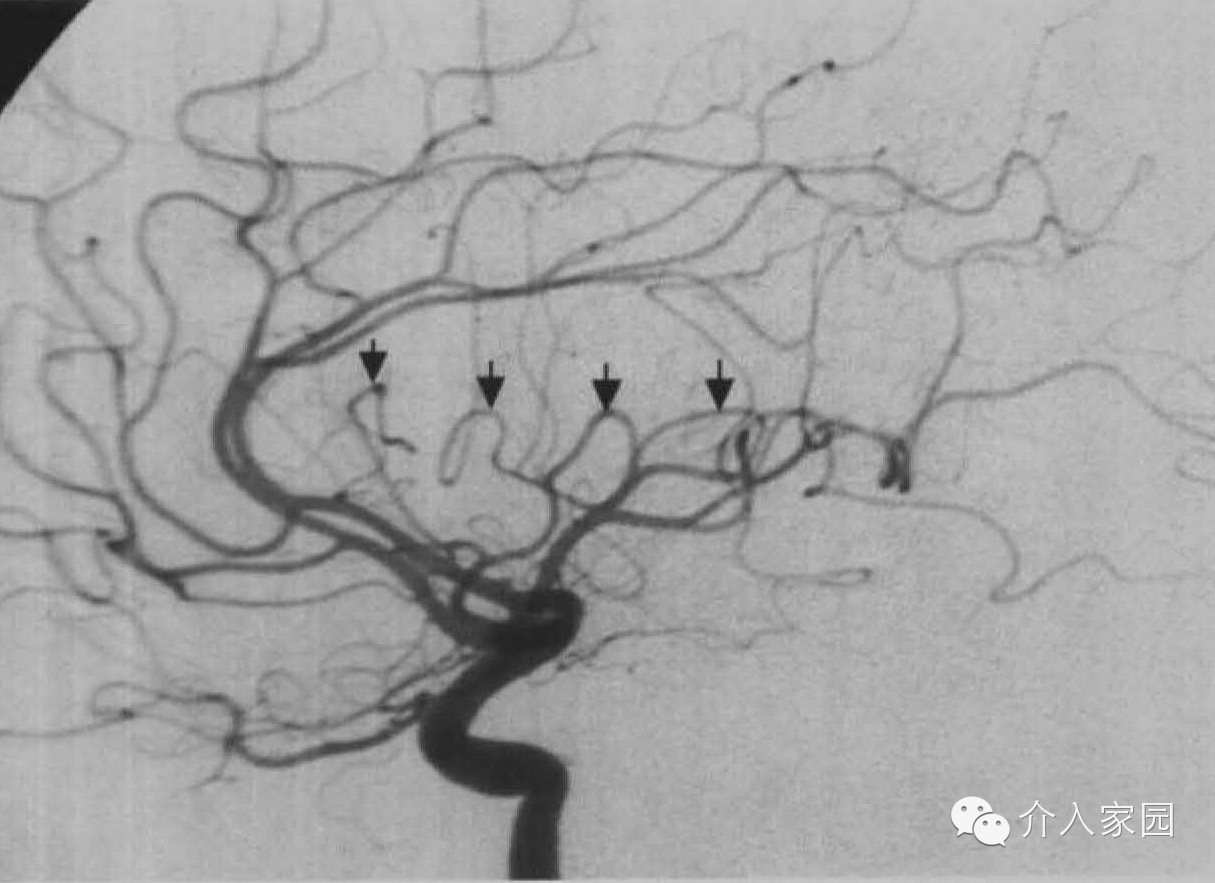

再來一張側位:

M2段 (小箭)向上走向環狀溝的頂端,這些袢頂相連應形成一相對的直線。